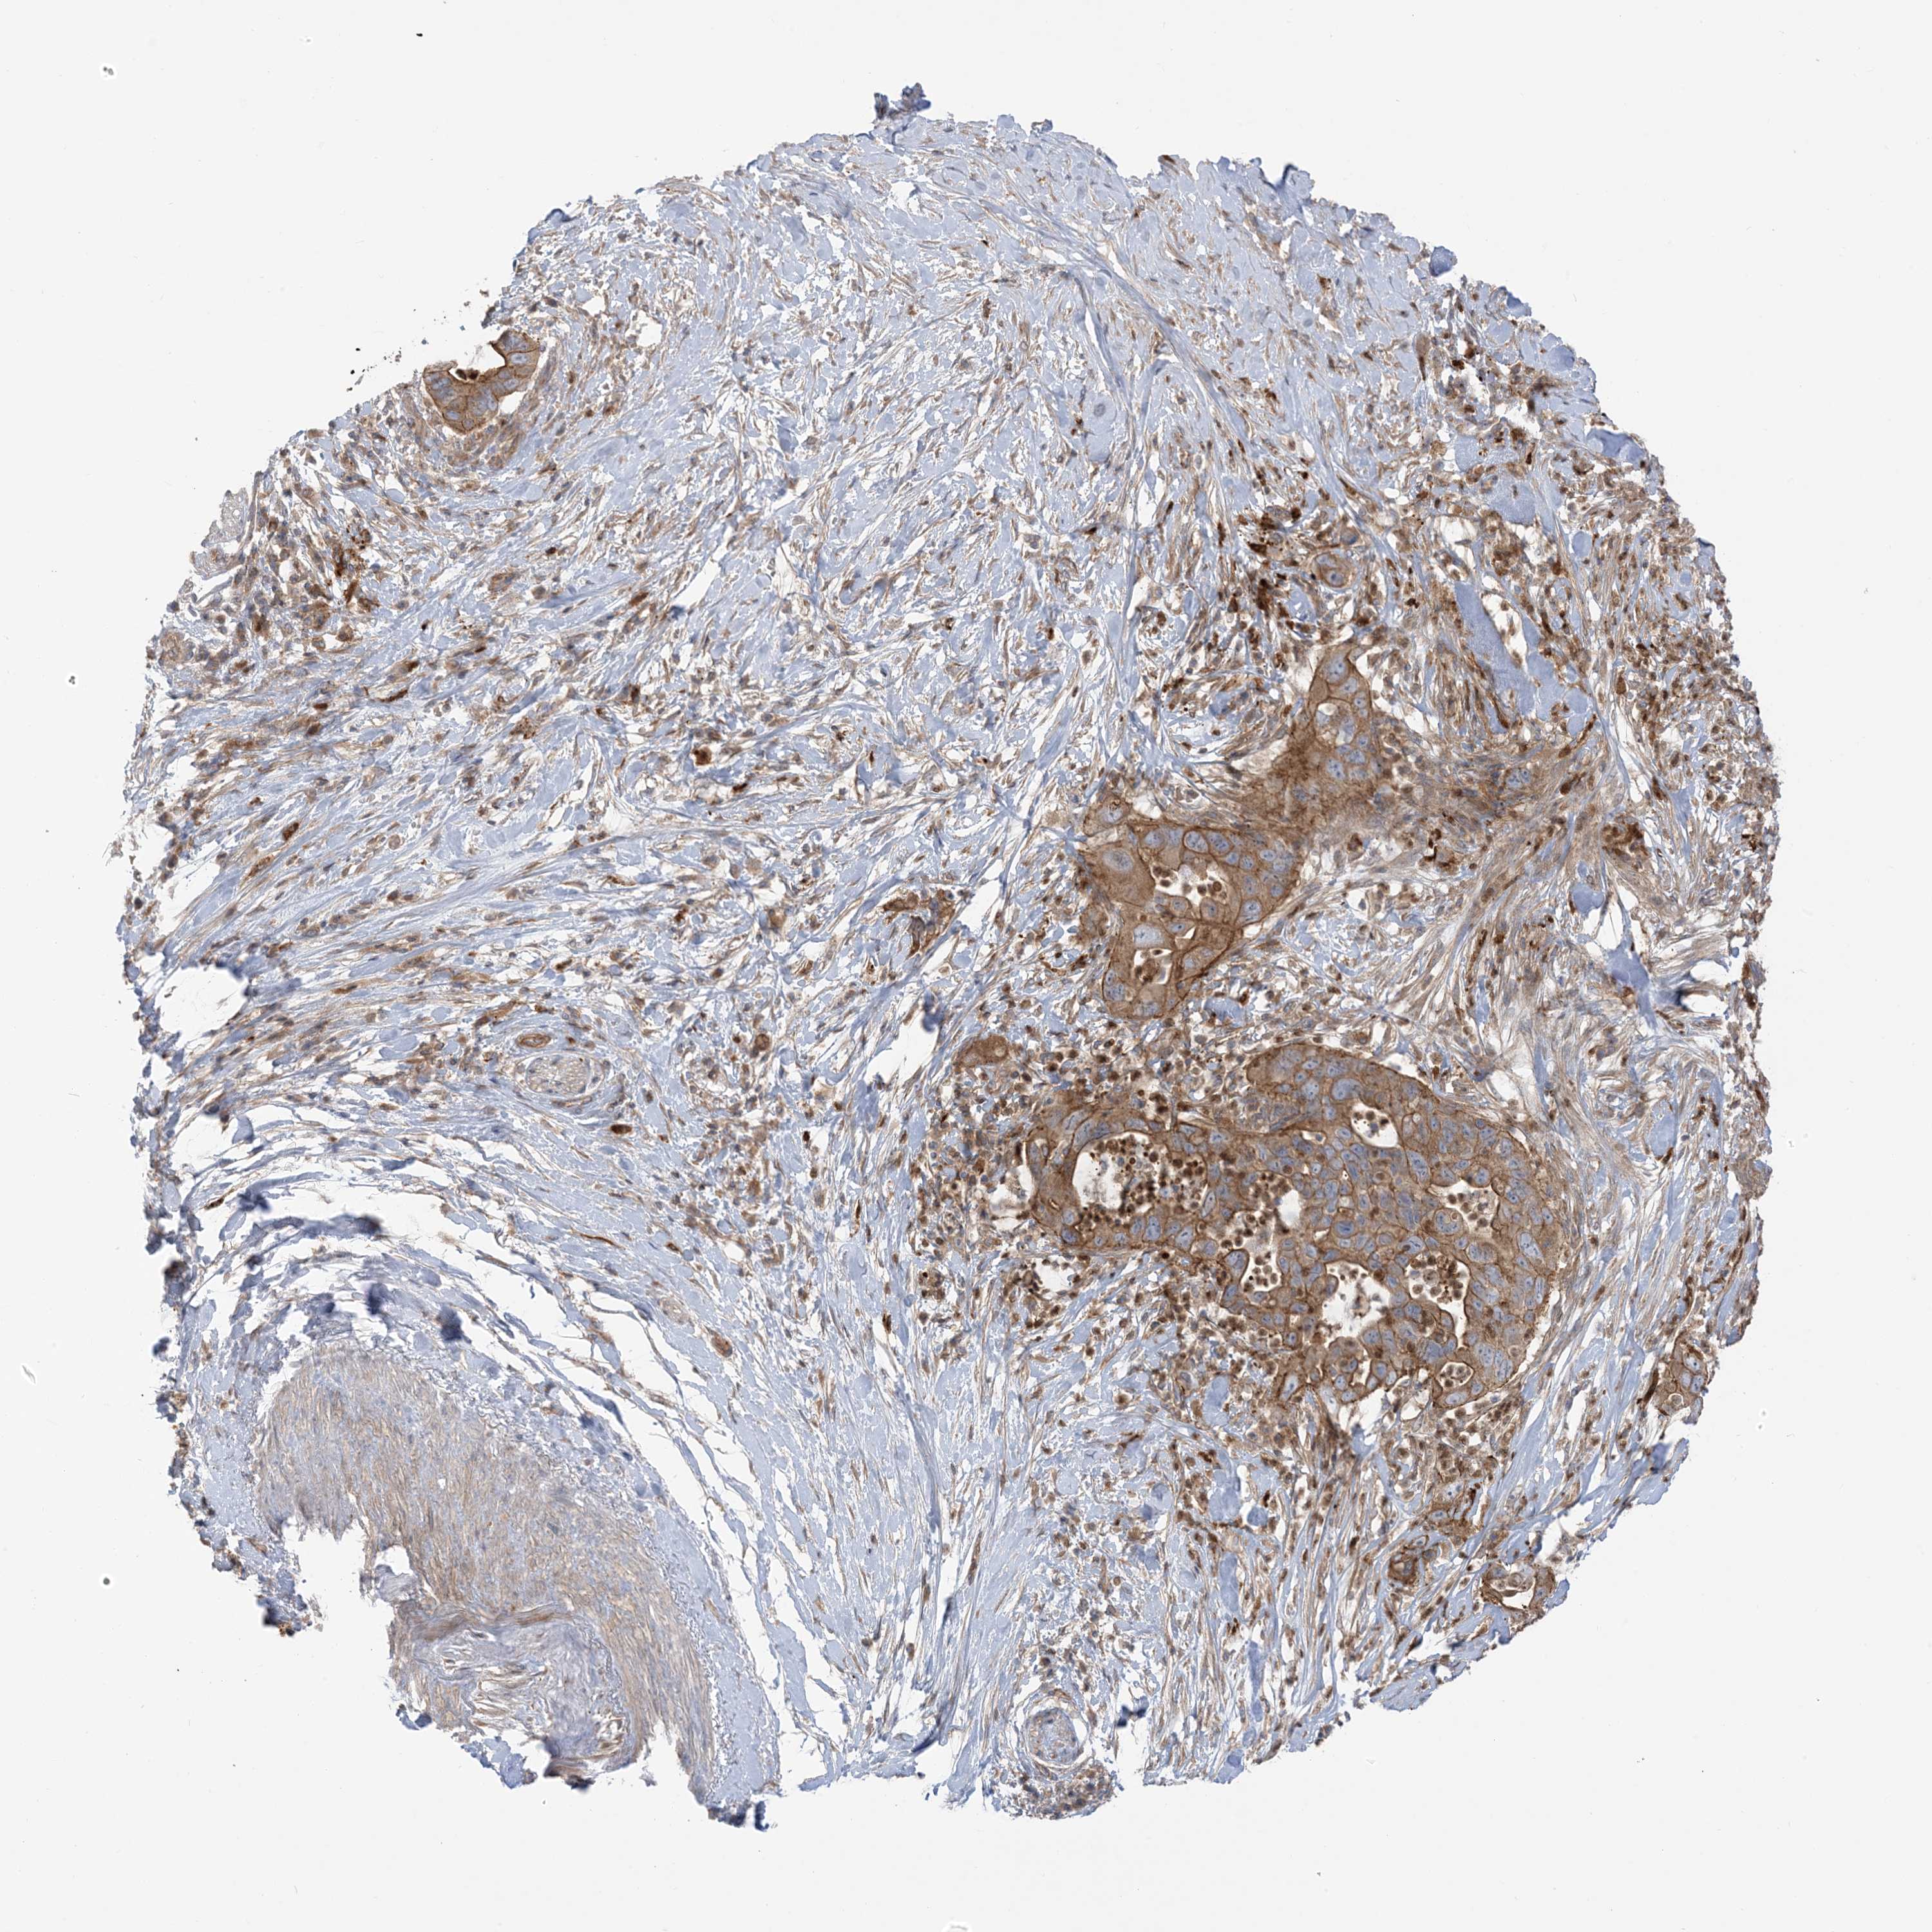

PANCREATIC CANCER - Protein expressioni

A mouse-over function shows sample information and annotation data. Click on an image to view it in a full screen mode. Samples can be filtered based on level of antibody staining by selecting one or several of the following categories: high, medium, low and not detected. The assay and annotation is described here.

Note that samples used for immunohistochemistry by the Human Protein Atlas do not correspond to samples in the TCGA dataset.

Antibody stainingi

Antibody staining in the annotated cell types in the current human tissue is reported as not detected, low, medium, or high, based on conventional immunohistochemistry profiling in selected tissues. This score is based on the combination of the staining intensity and fraction of stained cells.

Each image is clickable and will lead to virtual microscopy that enables deeper exploration of all samples and also displays staining intensity scores, fraction scores and subcellular localization as well as patient and tissue information for each sample.

Antibody HPA032024

Antibody HPA032025

Staining

High

Medium

Low

Not detected

Intensity

Strong

Moderate

Weak

Negative

Quantity

>75%

75%-25%

<25%

None

Location

Nuclear

Cytoplasmic/membranous

Cytoplasmic/membranous,nuclear

Adenocarcinoma, NOS